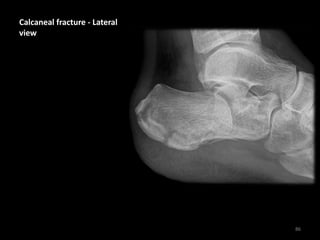

Calcaneal fracture - Lateral

view

• Flattening of Bohler's

angle (18° in this case)

• Depression of the

articular surface of the

posterior subtalar joint

(red line) from its

normal position (green

line)

• Fracture lines can be

seen passing through

the calcaneus

87